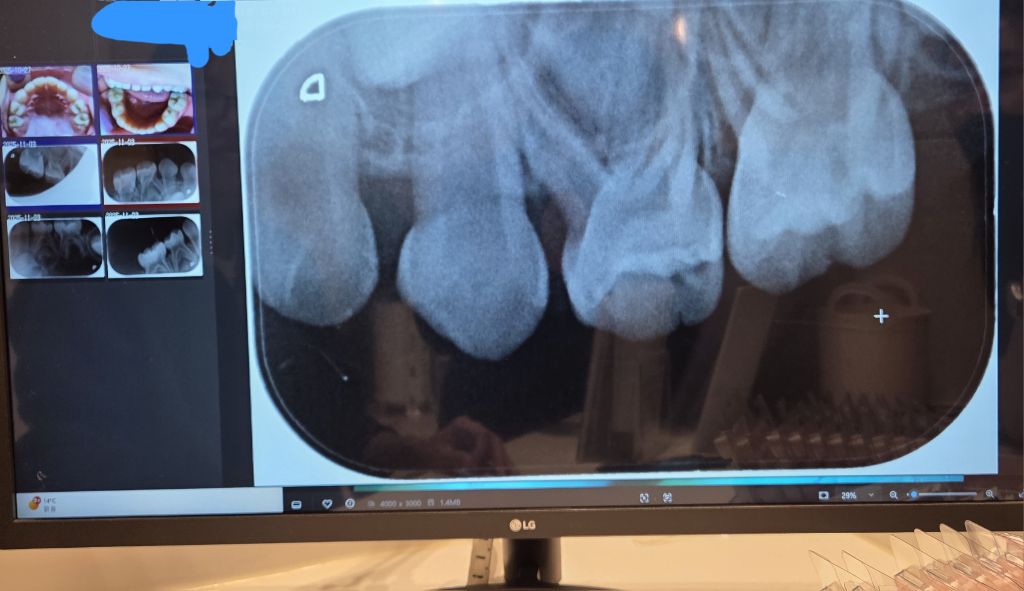

선생님 치과 방문도 계획했으나 전화문의 결과 너무 어려서 엑스레이 찍을 도구도 마땅치 않다는 안내에

일단 동네 어린이치과에서 엑스레이를 찍은 후 부탁해 사진을 받아 왔습니다.

이 치과에서는 모든 어금니에 충치가 다 있으나 (보는 사람 기준) 왼쪽 위에는 매우 약해서 치료를 안 해도 될 수는 있다고 했습니다만 나머지 6개는 모두 치료가 필요하다고 했습니다.

혹시 나머지 6개 어금니도 정말로 다 치료가 필요한 상황일까요?